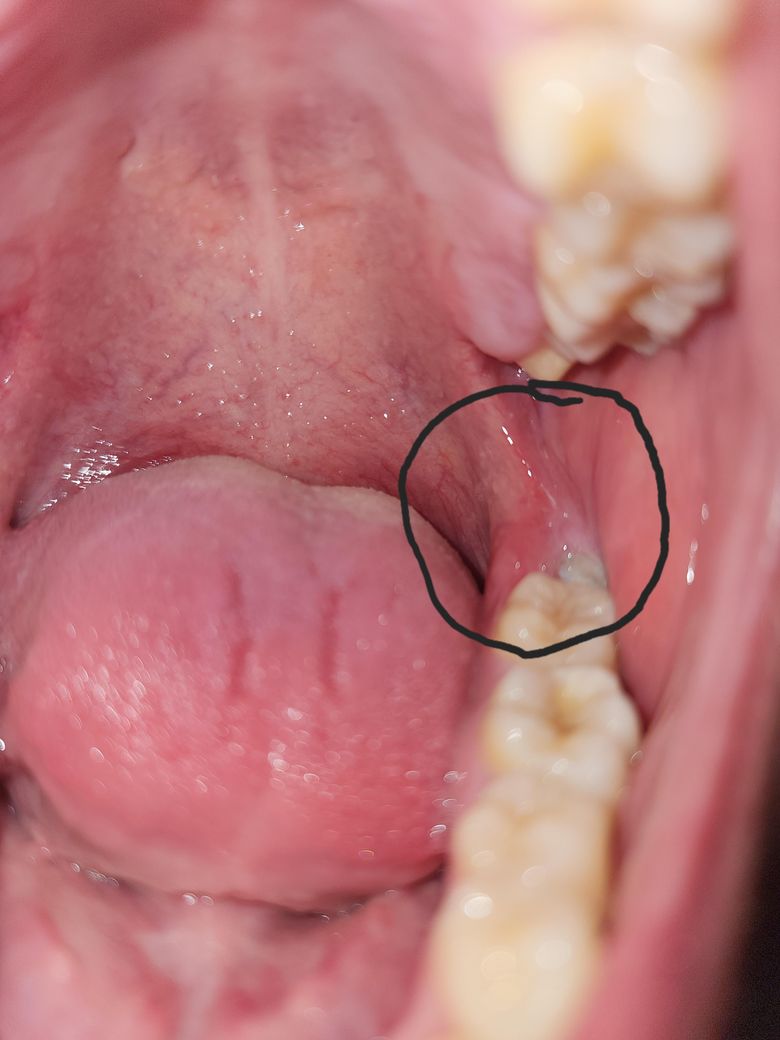

매복사랑니 주변 잇몸이 부었는데 심각하게 부은 상태인가요?

매복사랑니 주변 잇몸이 부었는데 심각하게 부은 상태인가요? 잇몸이 붓거나 통증있으면 발치하는게 좋다고 해서

이번 여름 지나면 뺄 예정입니다.

붓기 자체가 많아보이지는 않습니다만 통증이 느껴지고 있다면 사랑니 발치를 하시는 게 좋습니다.

잇몸이 많이 부은건 아니지만 불편하시면 일단 잇몸치료를 받아보시고 염증이 반복되면 발치를 하시는게 좋을것같습니다.

사진상으로는 심하게 부어보이지는 않으나, 방치시에는 염증이 심해질수 있기에 매복 사랑니는 빠른 시일내에 발치하길 권합니다.

막 심하게 붓지는 않았습니다 응급으로 빼야하는 정도는 아닙니다 발치 약속 전까지 그쪽으로 음식물 안끼게 관리만 잘해주시면 됩니다